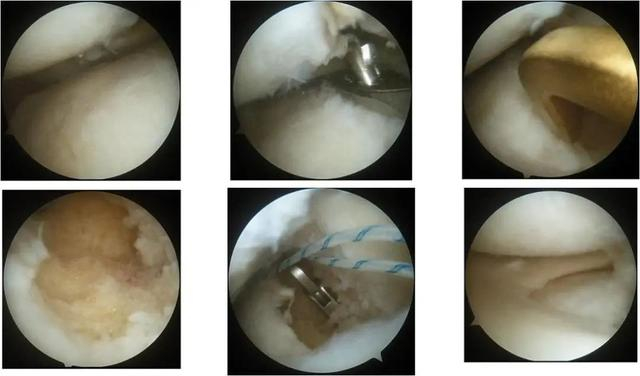

所移植的半月板假体

引入同种异体半月板,缝合器固定,镜下显示移植物与受体匹配良好

术后影像学显示移植半月板已填充在正常位置,匹配良好